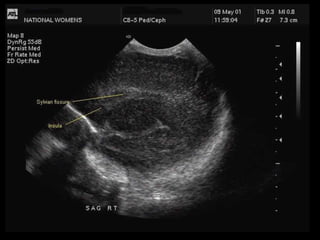

Tangential Parasagittal View:

Further angulation of the transducer laterally results in a section lateral to the lateral

ventricles. The Sylvian fissure is the key landmark in this view.

Tangential Parasagittal View: Furtherangulation of the transducer laterally results in a section lateral to the lateral ventricles. The Sylvian fissure is the key landmark in this view.